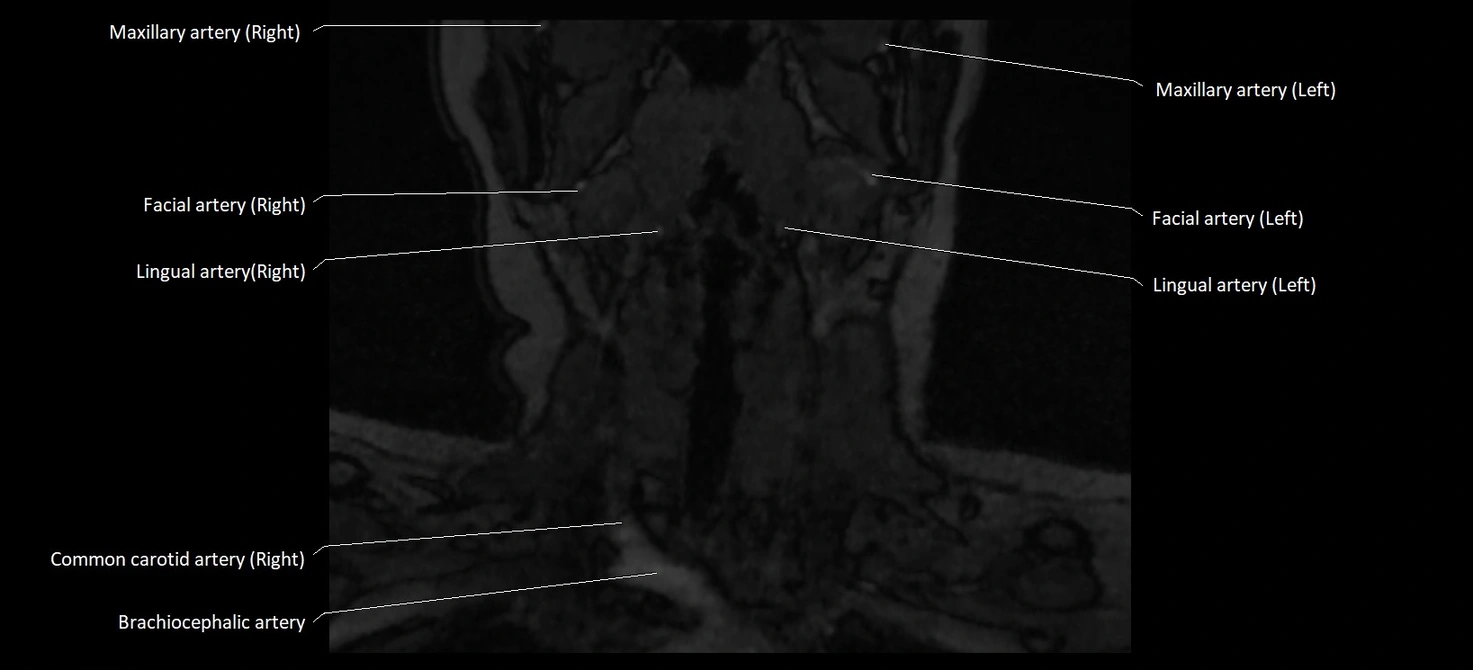

MRI images

image